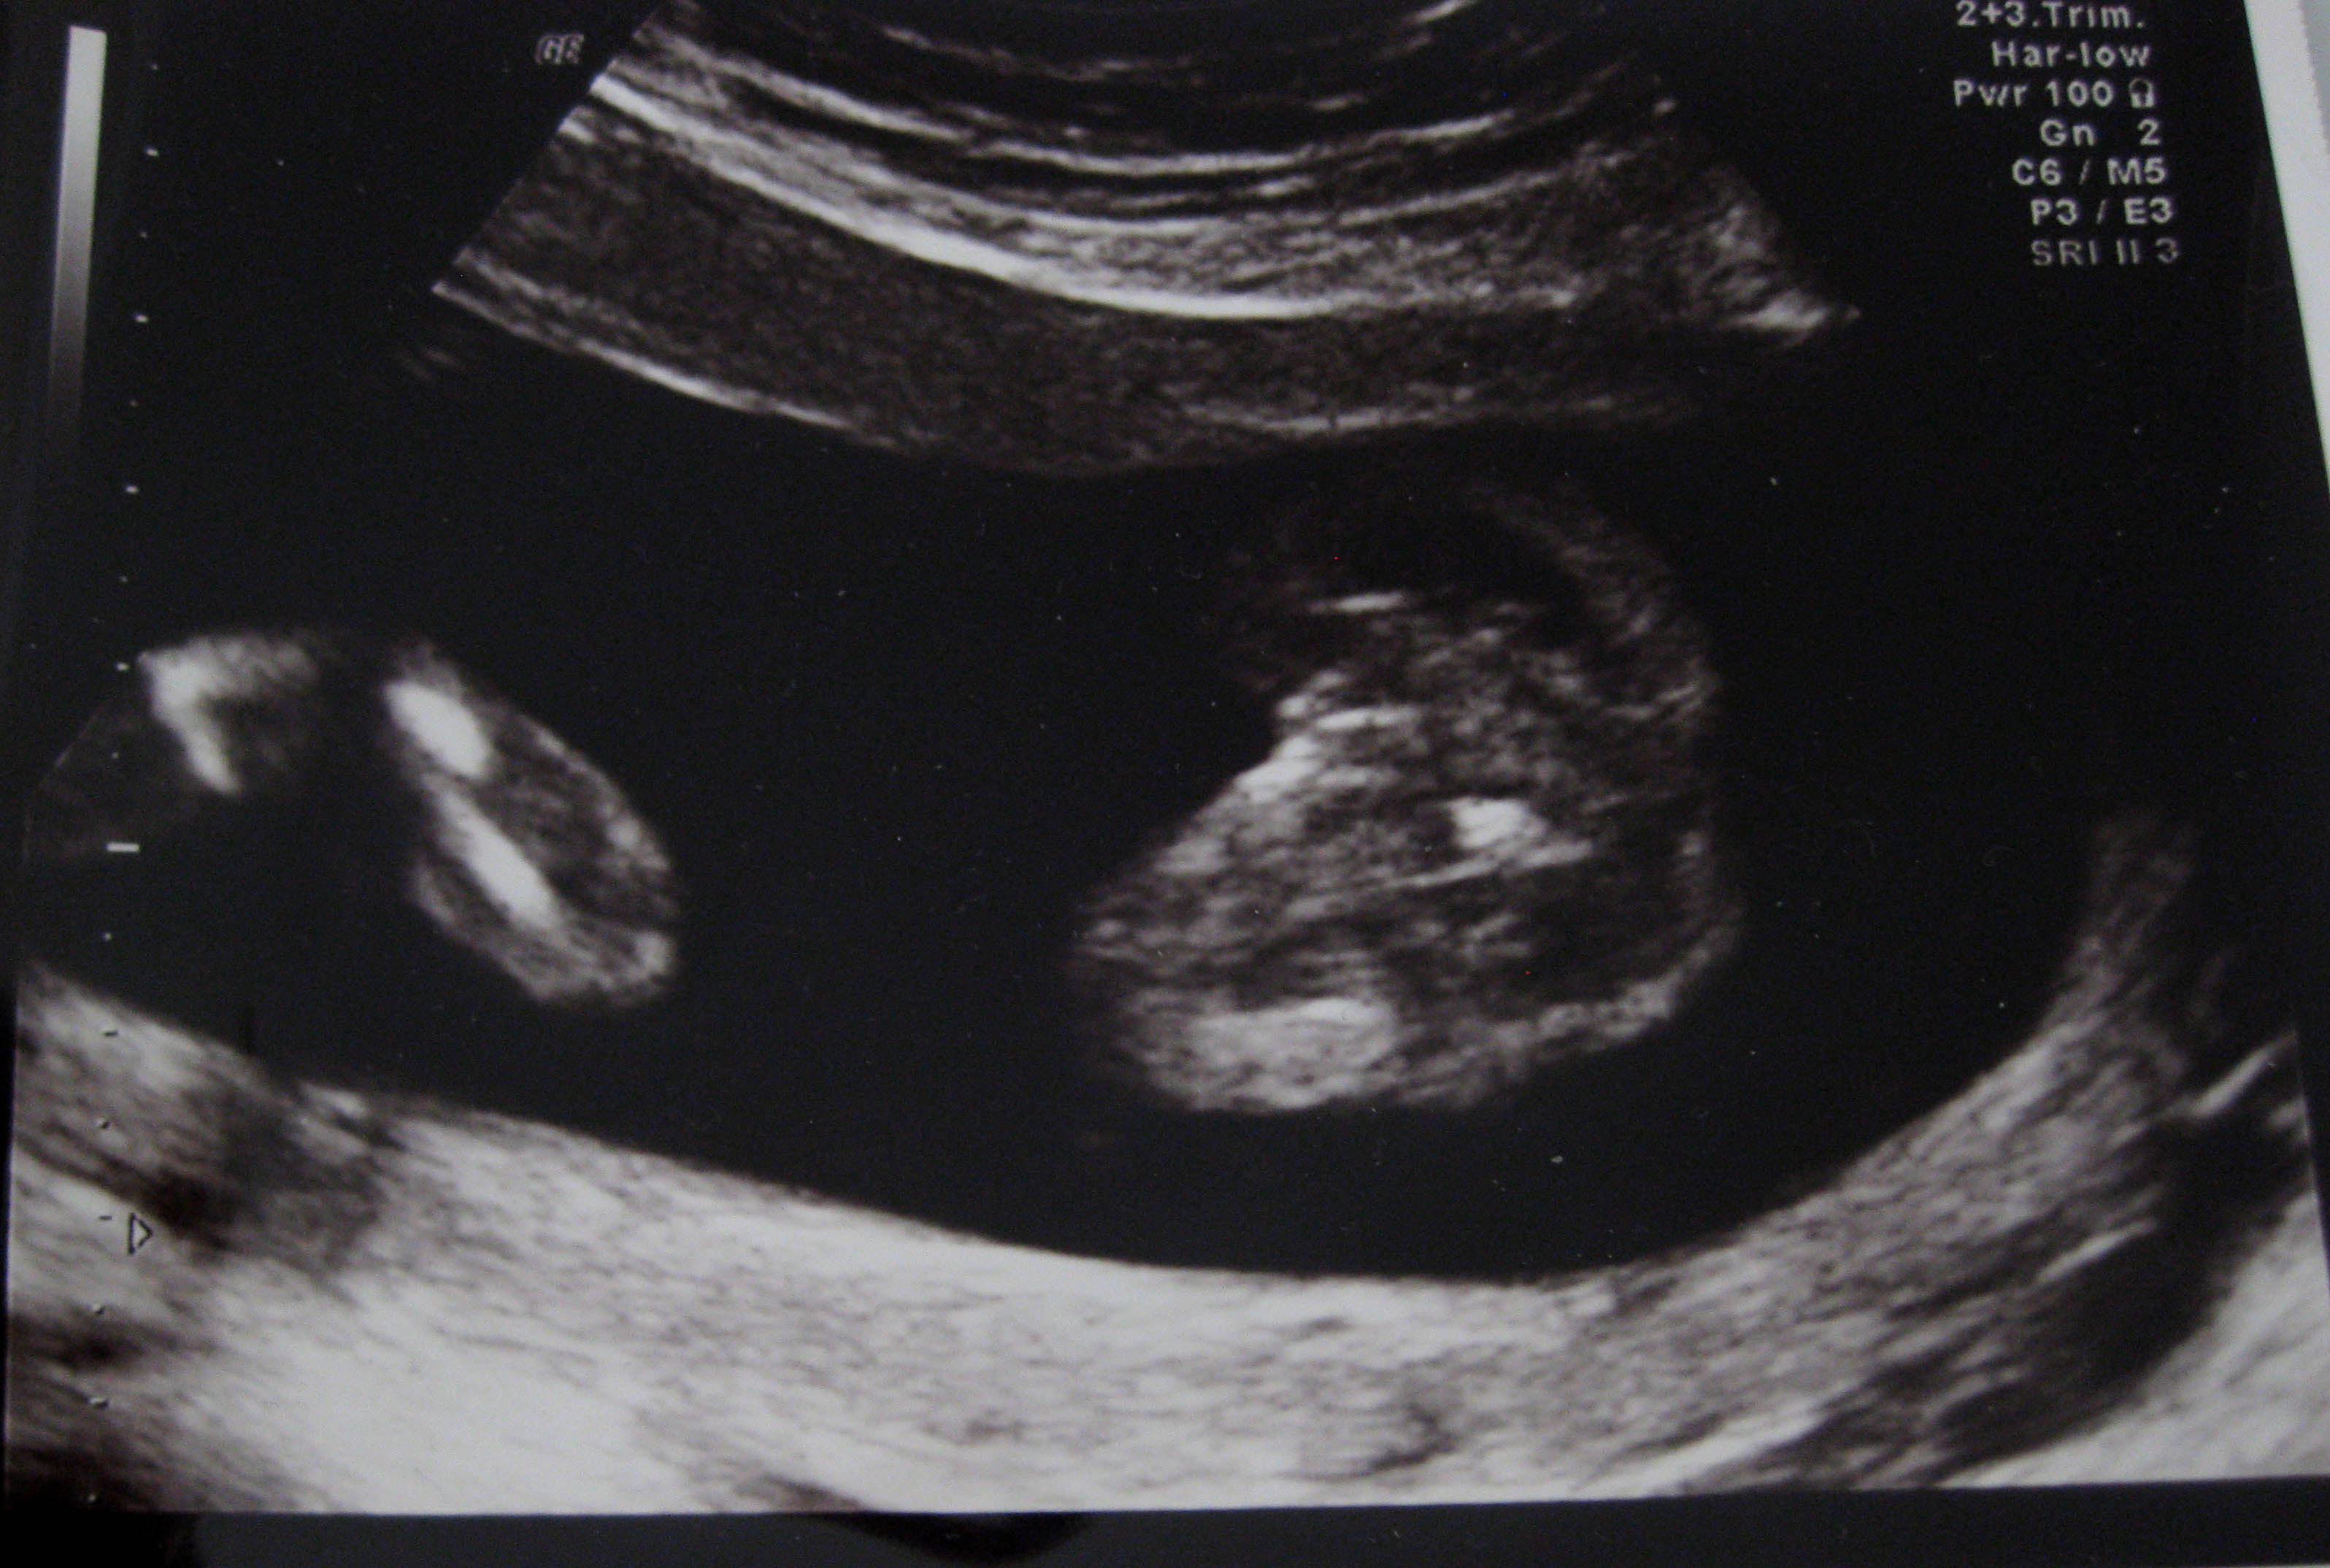

Here is my potty shot from my 20 weeks scan (now 24wks) The tech said over 90% sure was a girl but after 3 boys I still am finding it hard to believe. I keep thinking she missed something and it is really a boy.

What do yo think?

I can't tell what I'm looking at, sorry. :(

I don't think that pic is definitively girl, but if your tech said she is that sure, I'd take her word. There's certainly no sign of any boy parts, and I think by 20wks they couldn't be hiding *that* well!

I see a little tushie and then nothing on the other side!! Congrats, it's a girl!!

Guys, we're looking from bottom up. The blob on the right of the screen is the baby's bottom and genitals. The blob on the left is leg or foot possibly.

Girl 💗

I would be confident that this IS a GIRL :)

Yep thats a girl!!!!!!!!!!!!

I thought for a girl potty shot you had to be able to see three lines, that's what made me unsure but I'm not researched on potty shots yet! What( apart from absence of boy bits) tells you this is all girl?